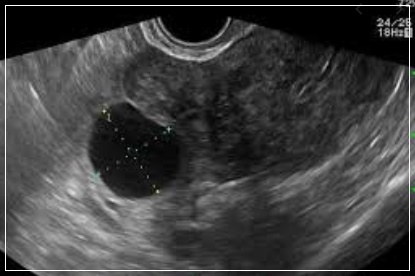

자궁,난소 등의 이상 소견을 확인하는 여성생식기 초음파 검사는 여성에서 흔히 발생하는 질환인 자궁근종, 난소 낭종 등을 진단하기 위한 기본적인 검사방법임에도 불구하고 그 동안 4대 중증질환(암·심장·뇌혈관·희귀난치)에 한해 제한적으로 건강보험이 적용됐 왔습니다.

특히나 자궁근종, 자궁내막증, 난소 낭종 등은 여성에서 흔히 발생하는 질환임에도 불구하고 건강보험이 적용되지 않았다. 전체 진료의 약 93%가 비급여로서 환자가 검사비 전액을 부담했습니다. 연간 비급여 규모는 약 3,300억 원으로 건강보험 적용 확대가 크게 요구되는 분야였습니다.